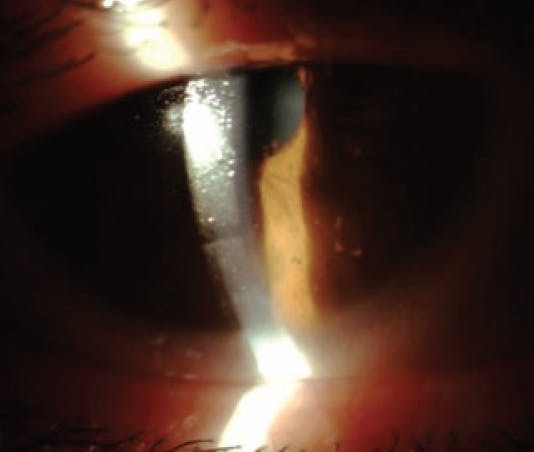

Overnight SCL wear is a well-established risk factor for microbial keratitis and other contact lens–associated corneal infiltrative events (Figure 1).3-11 In fact, there is as much as an eightfold increased risk of developing microbial keratitis with EW compared with daily wear contact lenses.11 The introduction of highly oxygen-permeable silicone hydrogel materials did not diminish the incidence of keratitis, and EW remains a risk factor for severe SCL complications across many lens materials and the frequency of overnight wear.7,8,10 Until new materials are developed that change the paradigm of EW risks, the fear of sight-threatening complications may prevent this modality from thriving.